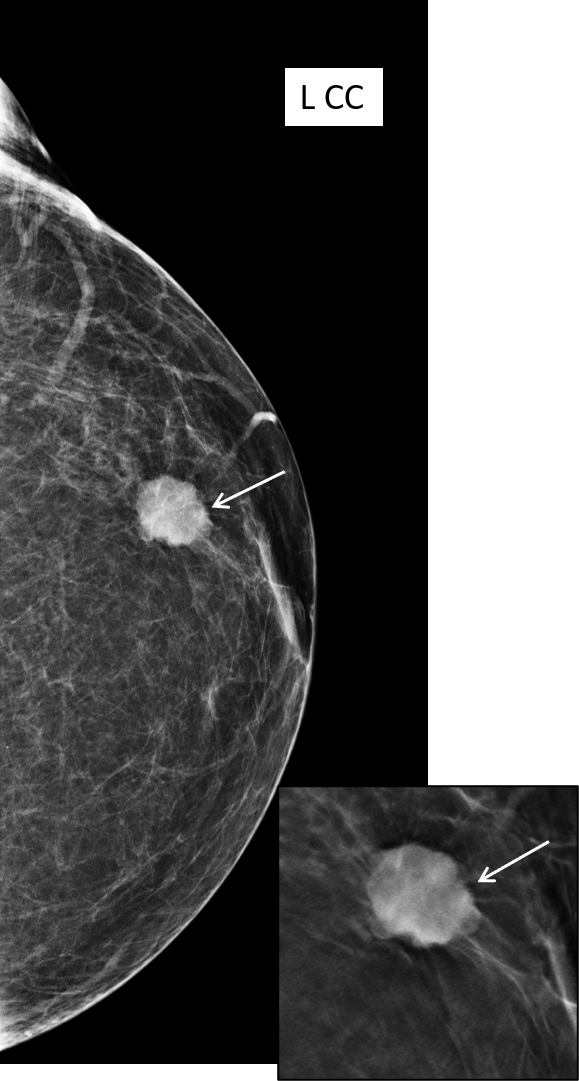

A postmenopausal woman who has previously been treated for contralater...

Read More